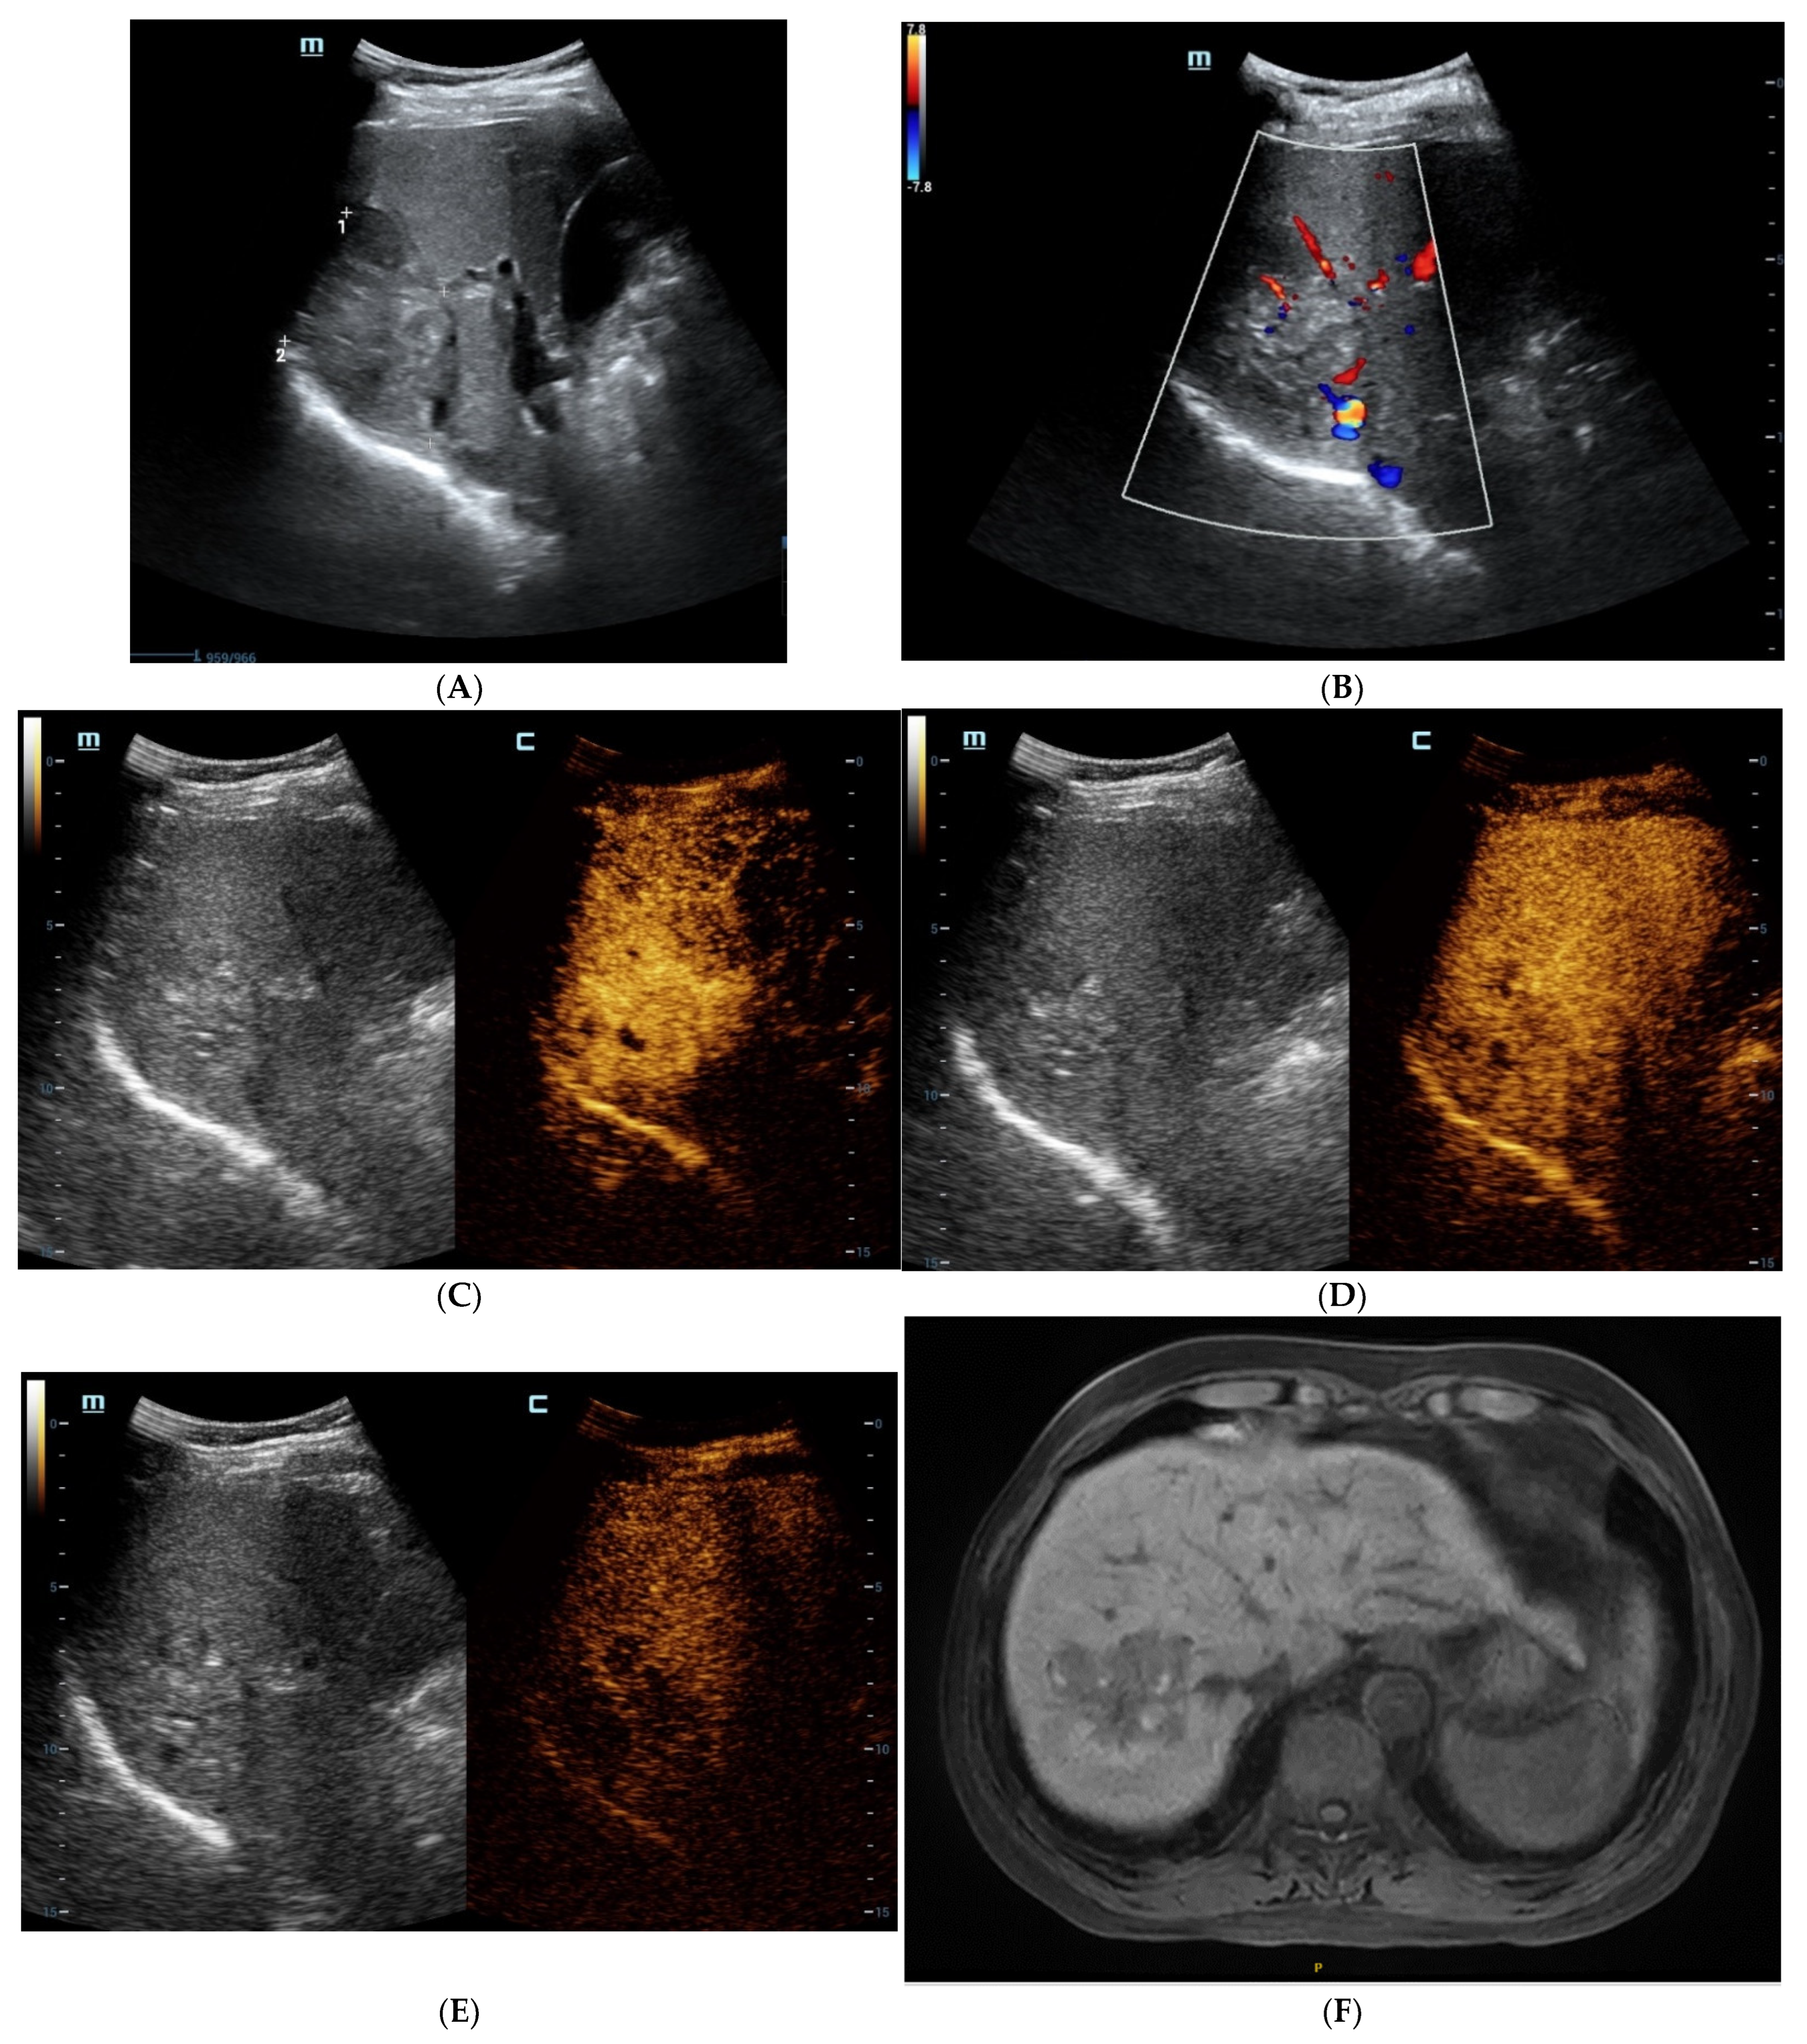

Figure 2.

The contrast-enhanced images of non-steatohepatitic hepatocellular carcinoma (non-SH-HCC). A hypo-echoic lesion in the right lobe of the liver was seen as seen via BMUS (A). In the early arterial phase of CEUS, the hepatic nodule was homogeneously hyperenhanced (B). During, it presented continuous iso-enhancement during the portal venous and late phase (C,D). On T1WI, the hepatic nodule was homogeneous hypointense (E). On T2WI, it was hypointense (F). As seen via con-trast-enhanced scan, the lesion showed hyperintensity in the arterial phase (G). It exhibited slight hyperintensity in the portal venous phase (H). During the late phase, the hepatic lesion started to show iso-intensity (I).